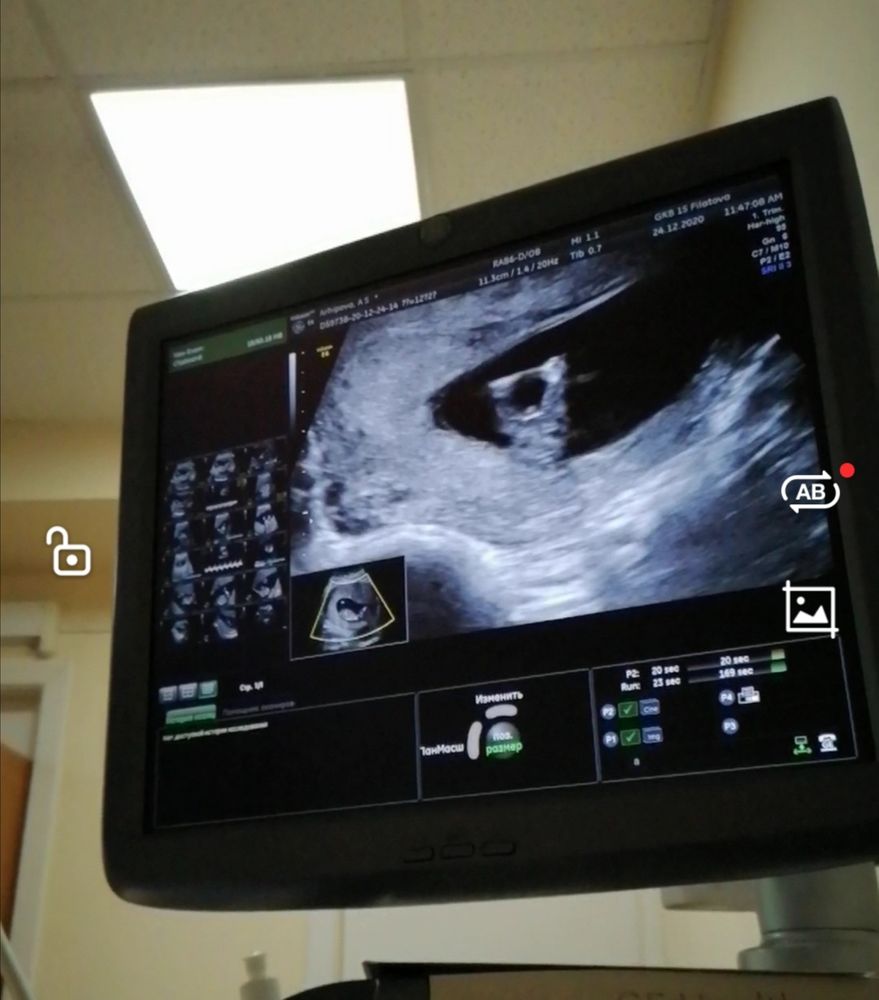

УЗИ в 12 недель.

На этом сроке смотрят только сбоку.

На этом сроке снизу смотреть нет смысла, потому что половой бугорок с этого ракурса одинаковый у всех)) А вот в профиль, по его наклону, можно увидеть.

Вот вид снизу Изображение

Елена, это вид снизу с попы? На мальчика похоже) мне показали вид и сбоку и снизу (прям половые губы видно было) был скрининг в 12 н 2 д

Maria , да это снизу, срок 12,3)) Врач мне сказала на мальчика похоже, но она не специалист по УЗИ беременным))